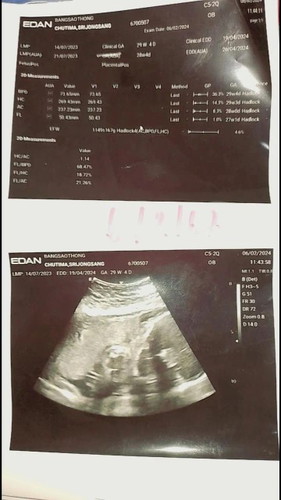

ช่วยดูให้หน่อยคะท้องแรกงงไปหมด

#ท้องแรกคะ ขอถามแม่ๆหน่อยคะต้องดูยังไงให้เป็นตัวน้องคะดูไปงงไป😅#ขอบคุณล่วงหน้านะคะ

วงกลมอันใหญ่จะเป็นส่วนศีรษะน้องค่ะส่วนก้อนเล็กๆข้างล่างจะเห็นแขนขาและช่วงลำตัวของน้องค่ะดูจากท่านอนค่ะ

ดูไม่ออกหรอกจ้า จะเป็นก้อนๆ ท้องสองแล้วยังดูไม่ออกเลย 555 ต้องดูตามหมอในจออัลตร้าซาวด์ค่ะ